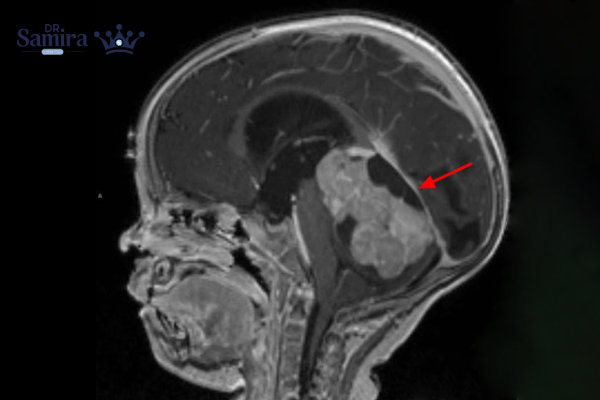

تشخیص با MRI مغز و ستون فقرات آغاز میشود؛ MRI علاوه بر نشان دادن توده، امکان بررسی انتشار در مسیر مایع مغزی نخاعی را فراهم میکند. پس از جراحی، بررسی پاتولوژی و آزمایشهای مولکولی برای تعیین زیرگروه و خطر ضروری است. همچنین نمونهگیری از مایع مغزی نخاعی (وقتی از نظر بالینی امن باشد) برای یافتن سلولهای توموری به مرحلهبندی کمک میکند. این مرحلهبندی تعیین میکند که آیا بیماری محدود به مخچه است یا به سایر نواحی CNS پخش شده است.

بهترین درمان برای مدولوبلاستوم

جراحی مخچه